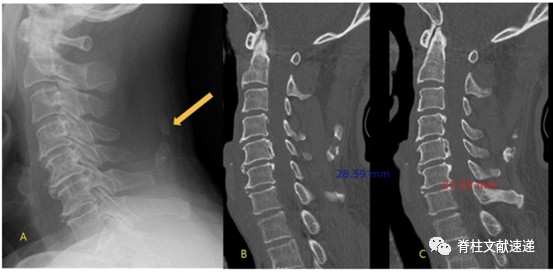

文献三

该文献进一步指出了项韧带骨化和OPLL的相关性,并举出3个病例,如下图。